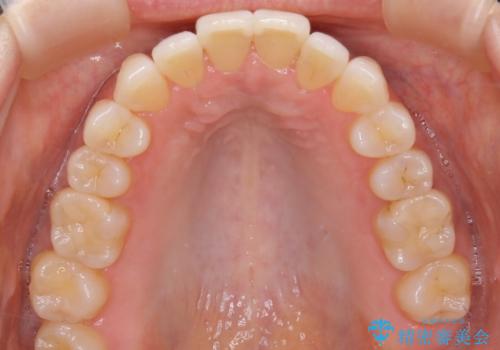

拡大とIPR

歯列の幅を拡大することにより作れるスペースは想像より大きく、実際に拡大だけでガタつきが治せるというケースもあります。

その他の歯のガタつきをとるためのスペース作りの方法の一つにディスキング(IPR)という方法があります。

歯と歯の間を一ケ所あたり最大0.5mmまでの範囲内で削ることで歯自体が少し小さくなり、それにより作られるスペースを数ヶ所分合わせることで合計で数mmの大きなスペースが作れるという方法です。

当院ではなるべく歯の機能や見た目に影響の出ないよう、作業時に拡大鏡の使用や削るタイミングの微調整を行っています。